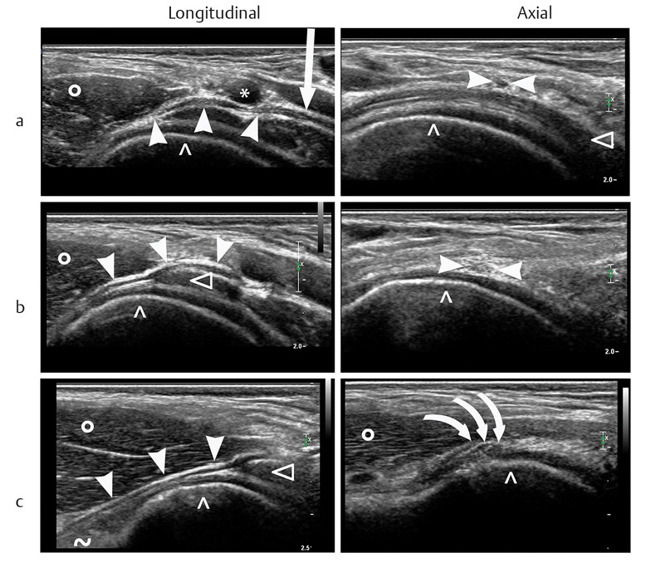

The surgical ultrasound section is a leader in the development of ultrasound techniques for the evaluation of peripheral nerves, ultrasound-guided nerve root infiltration and pain therapy. One of the most recent publications illustrates our work.

The axillary nerve (AN) is frequently injured during shoulder trauma and imaging is required to define the site and extent of nerve injury. However, the AN has a rather complex course through several soft tissue compartments of the shoulder and axilla. Detection and sonographic assessment therefore require thorough knowledge of the local topography.

Our investigation aims to define reliable, anatomical landmarks for AN sonography in volunteers and later to validate the proposed sonographic examination protocol in patients. With strict adherence to the proposed examination algorithm, sonography of the AN was feasible in all volunteers and patients. The findings correlated nicely with the gold standard of “surgical exploration” in respect of the severity and topography of neural impairment.

Based on our study results, we propose our algorithm for AN sonography as the first-line imaging tool for the assessment of axillary nerve trauma (PIC).